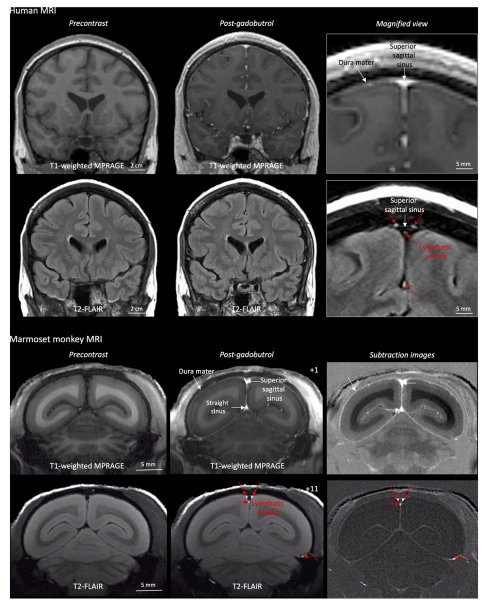

Пяти здоровым добровольцам ввели вещество под названием гадобутрол. Это контрастный реагент, который используют при магнитно-резонансной визуализации. Приборы настроили так, чтобы на изображение не попадали кровеносные сосуды. В итоге исследователи увидели разветвленную систему каналов.

«Я был очень удивлен. В медицинской школе нас учили, что мозг не имеет лимфатической системы», — рассказал автор исследования Даниэл Рейх. Теперь исследователи планируют подробнее изучить дренажную систему, чтобы узнать, как сбои в ее работе могут повлиять на здоровье.